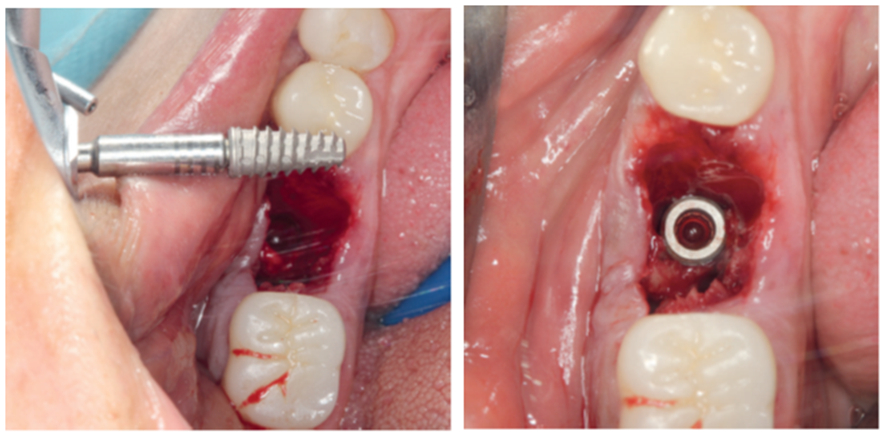

Para a instalação do implante imediato de corpo cônico cone-morse (Maestro, 4 mm x 9 mm, Implacil De Bortoli – São Paulo, Brasil), iniciou-se a fresagem de 9 mm com a fresa lança helicoidal 2.0, seguindo com a fresa cônica 3,5 mm x 9 mm com inclinação para mesial, na região mais centralizada entre a vestibular e a lingual do septo inter-radicular. Com o uso do Túnel Check Cônico 4.0 – instrumental que permite realizar a medição da profundidade da fresagem e sua inclinação –, verificou-se o paralelismo da perfuração para inserção do implante dentário (Figura 4). Em seguida, o implante dentário foi inserido com travamento final de 20 Ncm e recebeu o parafuso de cobertura correspondente (Figuras 5 e 6).